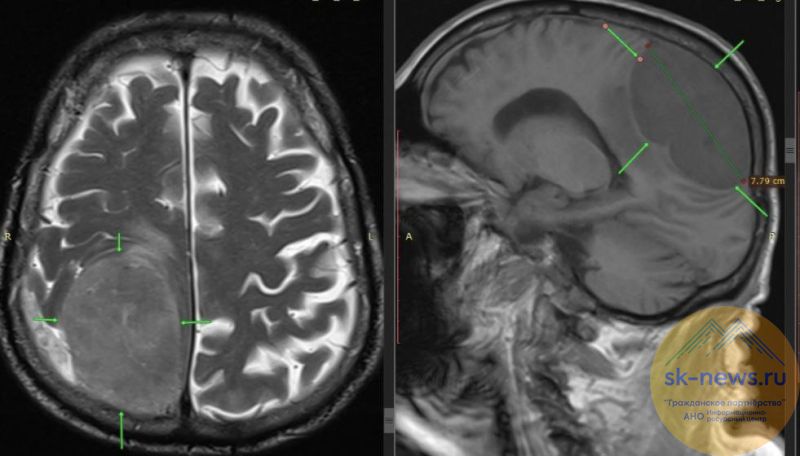

В Пятигорске врачи городской клинической больницы спасли 85-летнего мужчину, удалив ему опухоль мозга размером с крупный лимон.